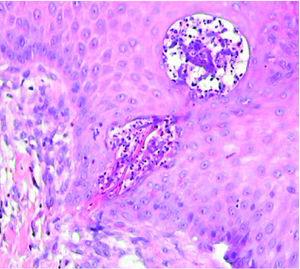

Se realizó cultivo de las lesiones, que se procesó para aerobios, anaerobios, micobacterias y hongos con resultado negativo. Se realizó, además, una biopsia cutánea; en el estudio histológico se apreciaba un epitelio con acantosis e hiperqueratosis, con una invaginación central ocupada por queratina ortoqueratósica y paraqueratósica, celularidad inflamatoria, material necrótico y elementos de tejido conjuntivo (fig. 2). En esta zona y a mayor aumento se observaban haces de colágeno dispuestos verticalmente y atravesando la epidermis. La dermis mostraba cambios degenerativos y un infiltrado inflamatorio mixto (fig. 3). No se apreció la localización folicular ni restos de folículo piloso, a pesar de la realización de múltiples cortes histológicos.

Fig. 3.--Se observan fibras de colágeno dispuestas verticalmente que atraviesan la epidermis, acompañadas de celularidad inflamatoria y detritus celulares. (Hematoxilina-eosina, ×20.)